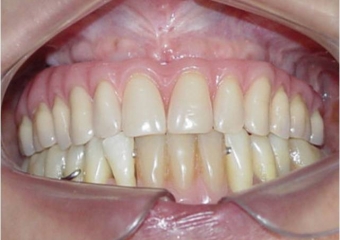

Sorriso final